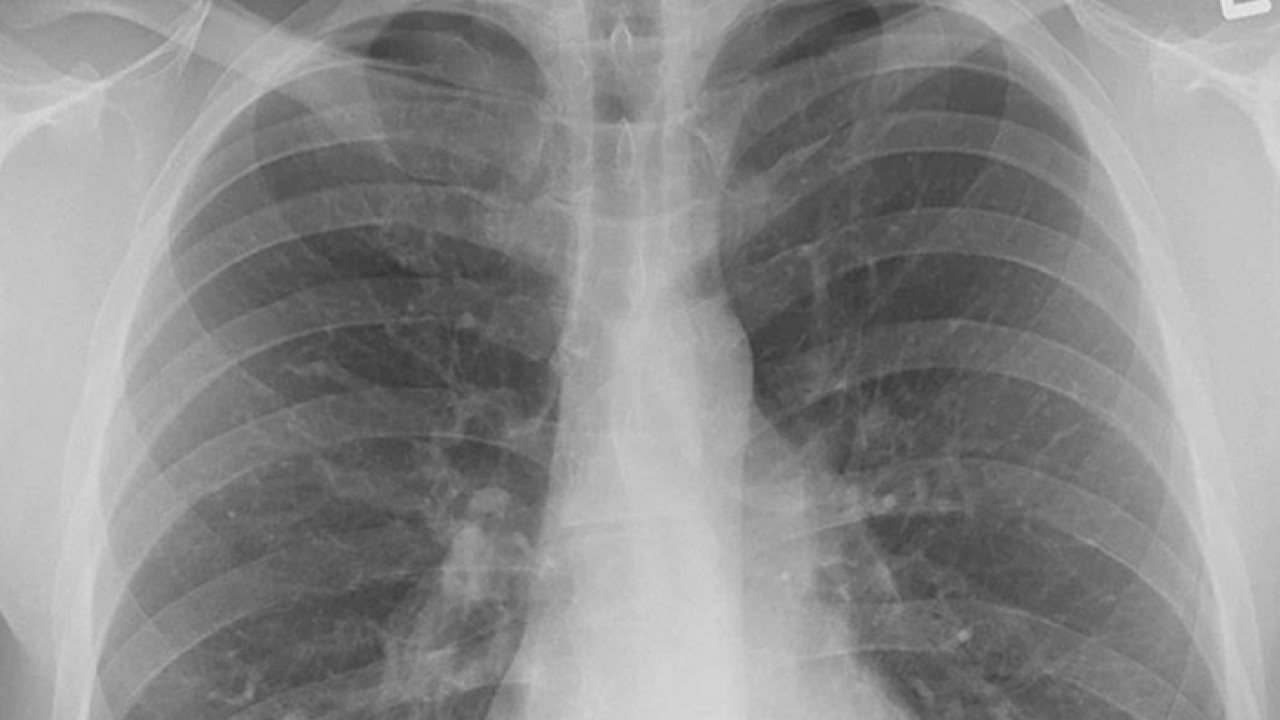

Genellikle akciğer kanserinin neden olduğu bulgu ve şikayetlerin oluşumu birkaç yıl alıyor ve bu nedenle hastalık ileri evreye gelinceye kadar fark edilemeyebiliyor. Kontrol veya başka bir rahatsızlık nedeniyle çekilen akciğer grafisinde kanser teşhis edilebiliyor, erken teşhis tedavide başarı olasılığını artırıyor.